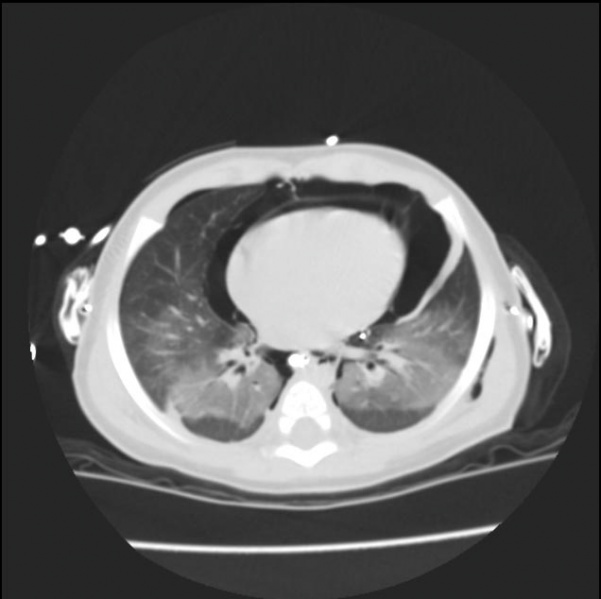

A 23 year-old woman came into the ER with severe chest pain and sob. We obtained a CTA chest to evaluate for pulmonary embolism. Instead of pulmonary embolism, the Radiologist found a pneumomediastinum on the patients left side and subcutaneous air continuing superiorly into the neck. The patient had no prior diagnosis of these conditions and had not experienced any trauma. Pneumomediastinum is not common and can be caused by several factors. These can include sudden altitude changes, trachea tear, inhalants, and trauma. Subcutaneous air or emphysema in the neck is usually a result of the pneumomediastinum. These images are examples of pneumomediastinum and subcutaneous emphysema.